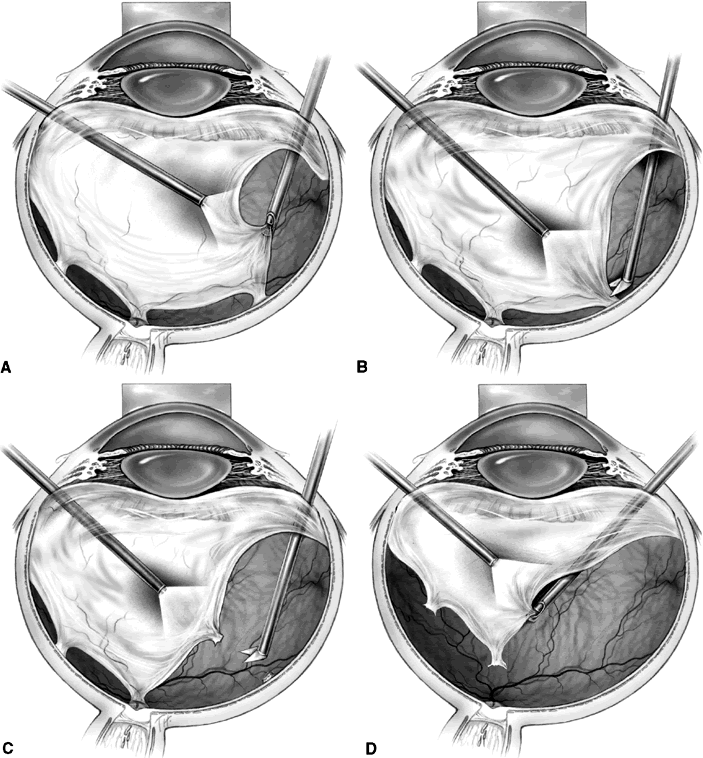

Delamination begins similarly to segmentation with the removal of the partially detached posterior vitreous surface between the vitreous base and the edge of the fibrovascular adhesions. Using bimanual techniques, from anterior to posterior, the edge of the fibrovascular membrane is reflected using either a lighted pick, lighted forceps, the light pipe, or a tissue manipulator (Fig. 2A). This allows the epicenters of adhesion between the retina and the fibrovascular membrane to be visualized. These epicenters then are amputated at the retinal surface using horizontal scissors, membrane peeling cutter scissors, or a diamond blade (see Fig. 2B). This technique is continued until all of the fibrovascular tissue has been removed up to the optic nerve head. The membrane then can be grasped with a forceps and gently avulsed (see Fig. 2C). Unlike segmentation, after membrane dissection using delamination technique, minimal or no epiretinal tissue remains on the retinal surface (see Fig. 2D). In cases with broad areas of severe vitreoretinal adhesion, a combination of delamination and segmentation may be necessary.

Fig. 2. A. A lighted pic is used to elevate and reflect the edge of epiretinal tissue so that foci of fibrovascular adhesion can be visualized. B. Horizontal scissors are used to amputate the fibrovascular adhesion at the retinal surface. C. After the epiretinal membrane has been dissected up to the optic nerve, forceps are used to grasp the membrane and gently avulse it from the optic nerve head. D. The epiretinal membrane has been completely removed, and panretinal endophotocoagulation is applied.